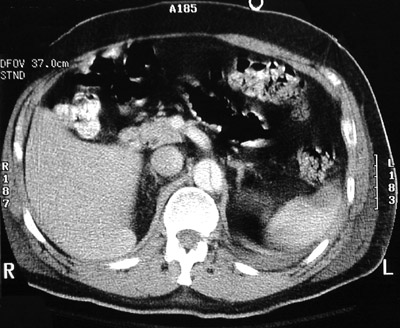

| These abdominal CT scan views above and below demonstrate an aortic dissection proceeding to the descending aorta. The superior mesenteric artery branch also appears to be affected. The classic historical finding of sudden, severe, "knife-like" pain in the chest or upper abdomen is more likely to be present in this situation. |